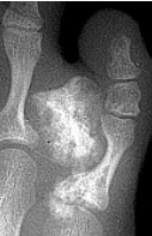

What disease is this? | Gout |

What disease is this? What do the arrows indicate? | Gout Arrows = 'punched out' erosions |